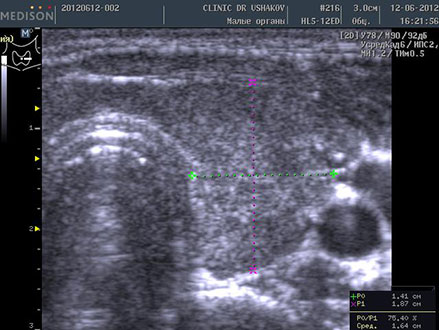

Пациентка К., 39 лет. При обследовании выявлены явления гипотиреоза и аутоиммунного тиреоидита. Через 1,5 года после лечебных мероприятий (в Клинике и соблюдение благоприятных условий) вместе с улучшением самочувствия произошло значительное восстановление щитовидной железы. В период лечения в связи с компенсированностью организма и гормонального обмена (Т4св. и Т3св.) и оздоровительным образом жизни медикаменты не применялись.

До лечения тиреоидита Анализ крови 9.06.2012 ТТГ 32 мЕд/л, Т4 св. 0,85 нг/дл АТ-ТПО 2113 ЕД/л | После лечения тиреоидита Анализ крови 15.01.2014 ТТГ 3,09 мЕд/л, Т4 св. 1,09 нг/дл АТ-ТПО 31,8 ЕД/л |

| В левой доле заметны: 1) значительно выраженная лимфоидная инфильтрация вдоль передней (вентральной) части доли и в перешейке ― признак аутоиммунного процесса, 2) единичные мелко- и среднеточечные очаги истощения и разрушения ткани. | В левой доле ткань восстановилась: 1) почти полностью исчезла значительная лимфоидная инфильтрация (заметна лишь очень мало выраженная гипоэхогенная зона у переднего края доли) ― устранение аутоиммунного процесса, 2) почти утилизировались очаги истощения, 3) восстановился объём |